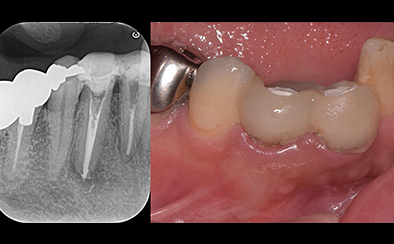

治療前

治療後

黄色い矢印の歯が治療前の対象歯です。レントゲンで観察すると、歯の根のお薬が充分には入っていないようです。

麻酔をして歯の中をマイクロスコープで観察すると、元々あった3つの根だけでなく「もう一つの4番目の根」があったのです。根管治療自体は容易に行えましたが、歯の中を明るく拡大できるマイクロスコープを持っていない歯医者さんでは見つけるのが困難だと思われます。この4つ目の歯の根を治療することにより痛みは消失し「抜歯してインプラント」になるという悪循環に陥らず済みました。根管治療はマイクロスコープを使って精密に、また丁寧に行えば歯を長く保たせることができる治療です。やはり神経自体を残すという選択が、歯の保存にとって一番良いということは間違いありません。

| 費用 | デンタルドック:55,000円 根管治療(奥歯):176,000円 MTAセメント:33,000円 歯の土台:33,000円 合計:297,000円 |

| リスク・副作用 | 治療中に一時的な咬合痛や冷温水痛、若干の歯肉の腫れ、発赤などを生じることがあります。また仮歯の時期には仮歯の脱離や破損の可能性、舌感などに違和感を覚えることがありますが、本歯に移行するまでに通常消失します。 ※すべて症例による違いや個人差があります。 |

※表示金額は全て税込みです。